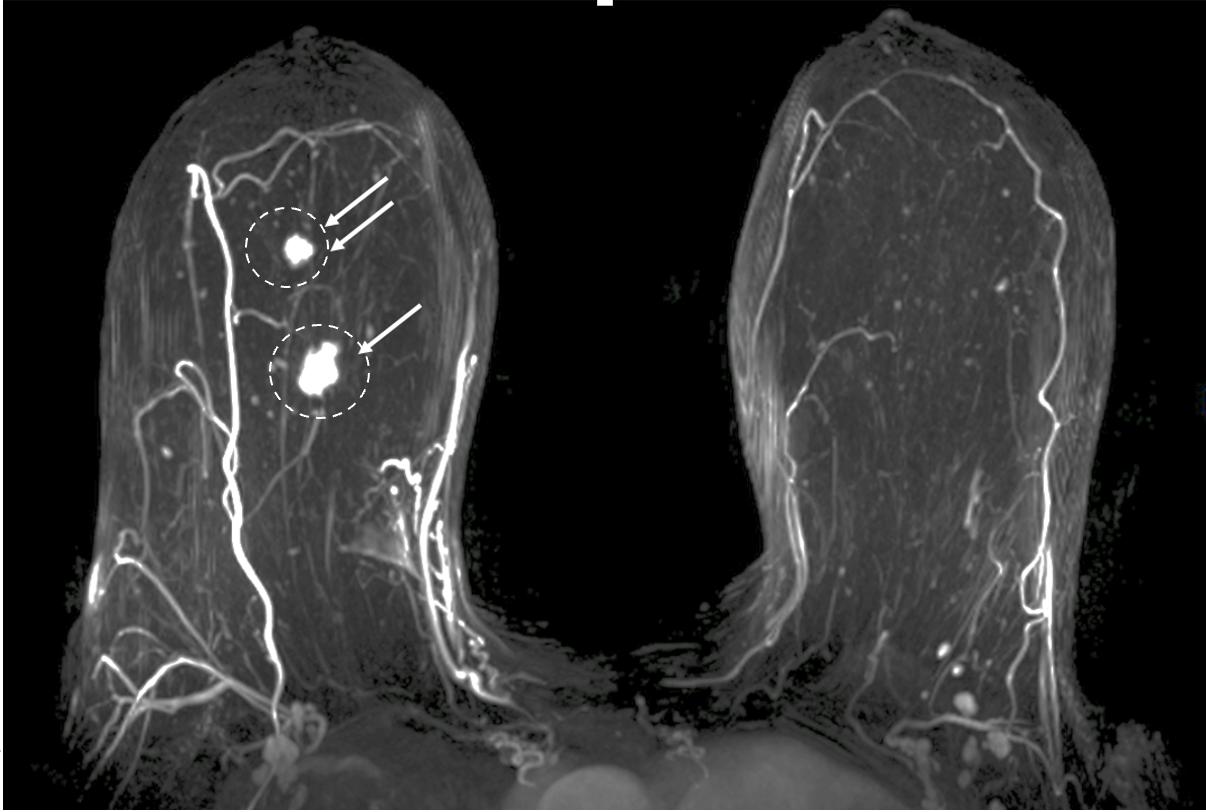

Contrast-Enhanced Breast MRI. Contrast enhanced Breast MRI improves assessment of disease extent, including detection of spiculations, multifocal, multicentric, or contralateral disease, which might impact eligibility for cryoablation or alter the overall treatment plan (Image 4). Contrast-enhanced breast MRI has the added value of permitting 3-D image reconstruction to permit viewing of the tumor from various angles for a more comprehensive assessment of tumor shape and size. Breast MRI for cancer evaluation requires use of an intravenous contrast containing gadolinium that can be safely administered with minimal short-term and long-term risks. However, patients unwilling or unable to receive gadolinium might be able to access dedicated breast-only diffusion weighted MRI, which has limited availability in the U.S.

Image 4. Contrast-enhanced breast MRI image showing multifocal disease indicated by mass-like enhancement of dominant mass (indicated by single arrow and encircled with hash marks) as well as mass-like enhancement of a second focus of disease (indicated by double arrows and encircled with hash marks). The second focus was mammographically-occult.